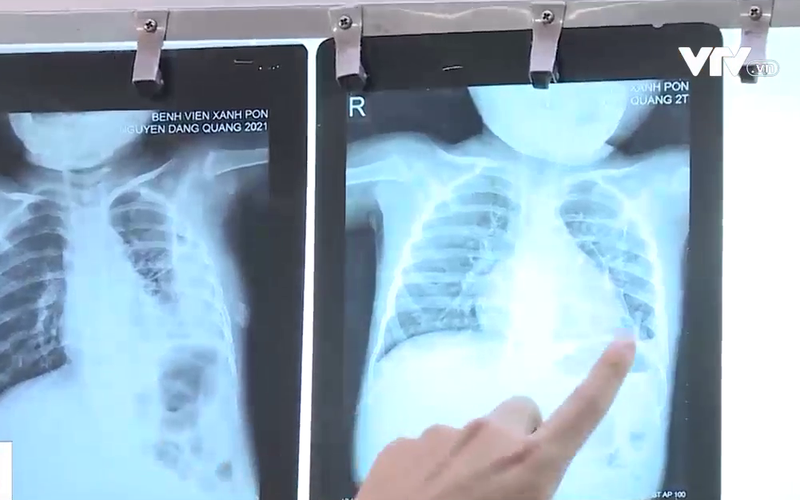

Bệnh nhi này vừa trải qua cơn nguy kịch sau gần 1 tháng điều trị viêm phổi do tụ cầu. Đáng nói trước đó, bé sốt khoảng chục ngày nhưng gia đình vẫn không phát hiện ra bệnh. Chỉ từ nốt nhọt ở gót chân, bệnh nhi xuất hiện tình trạng áp xe phổi, viêm màng phổi.

Chị Đỗ Thảo Ly, TP. Hà Nội cho biết: “Chụp phim đã bị mưng mủ trắng hết bên phổi rồi. Chỉ có 2 nốt thôi rất to nên không biết cách điều trị như nào”.

TS.BS. Phan Thị Kim Dung – Phó trưởng khoa Nhi hô hấp, Bệnh viện Đa khoa Xanh Pôn cho biết: “Sẽ tìm thấy những ổ trên da, mụn nhọt do tụ cầu, sau đó trẻ mới có những biểu hiện về hô hấp. Trên da mà có ban hay nhọt như thế, đôi khi cha mẹ không đi khám bệnh thì dễ nhầm lẫn vấn đề liên quan đến virus như chân tay miệng hay ban khác mà đôi khi họ ko biết tưởng là sốt xuất huyết”.